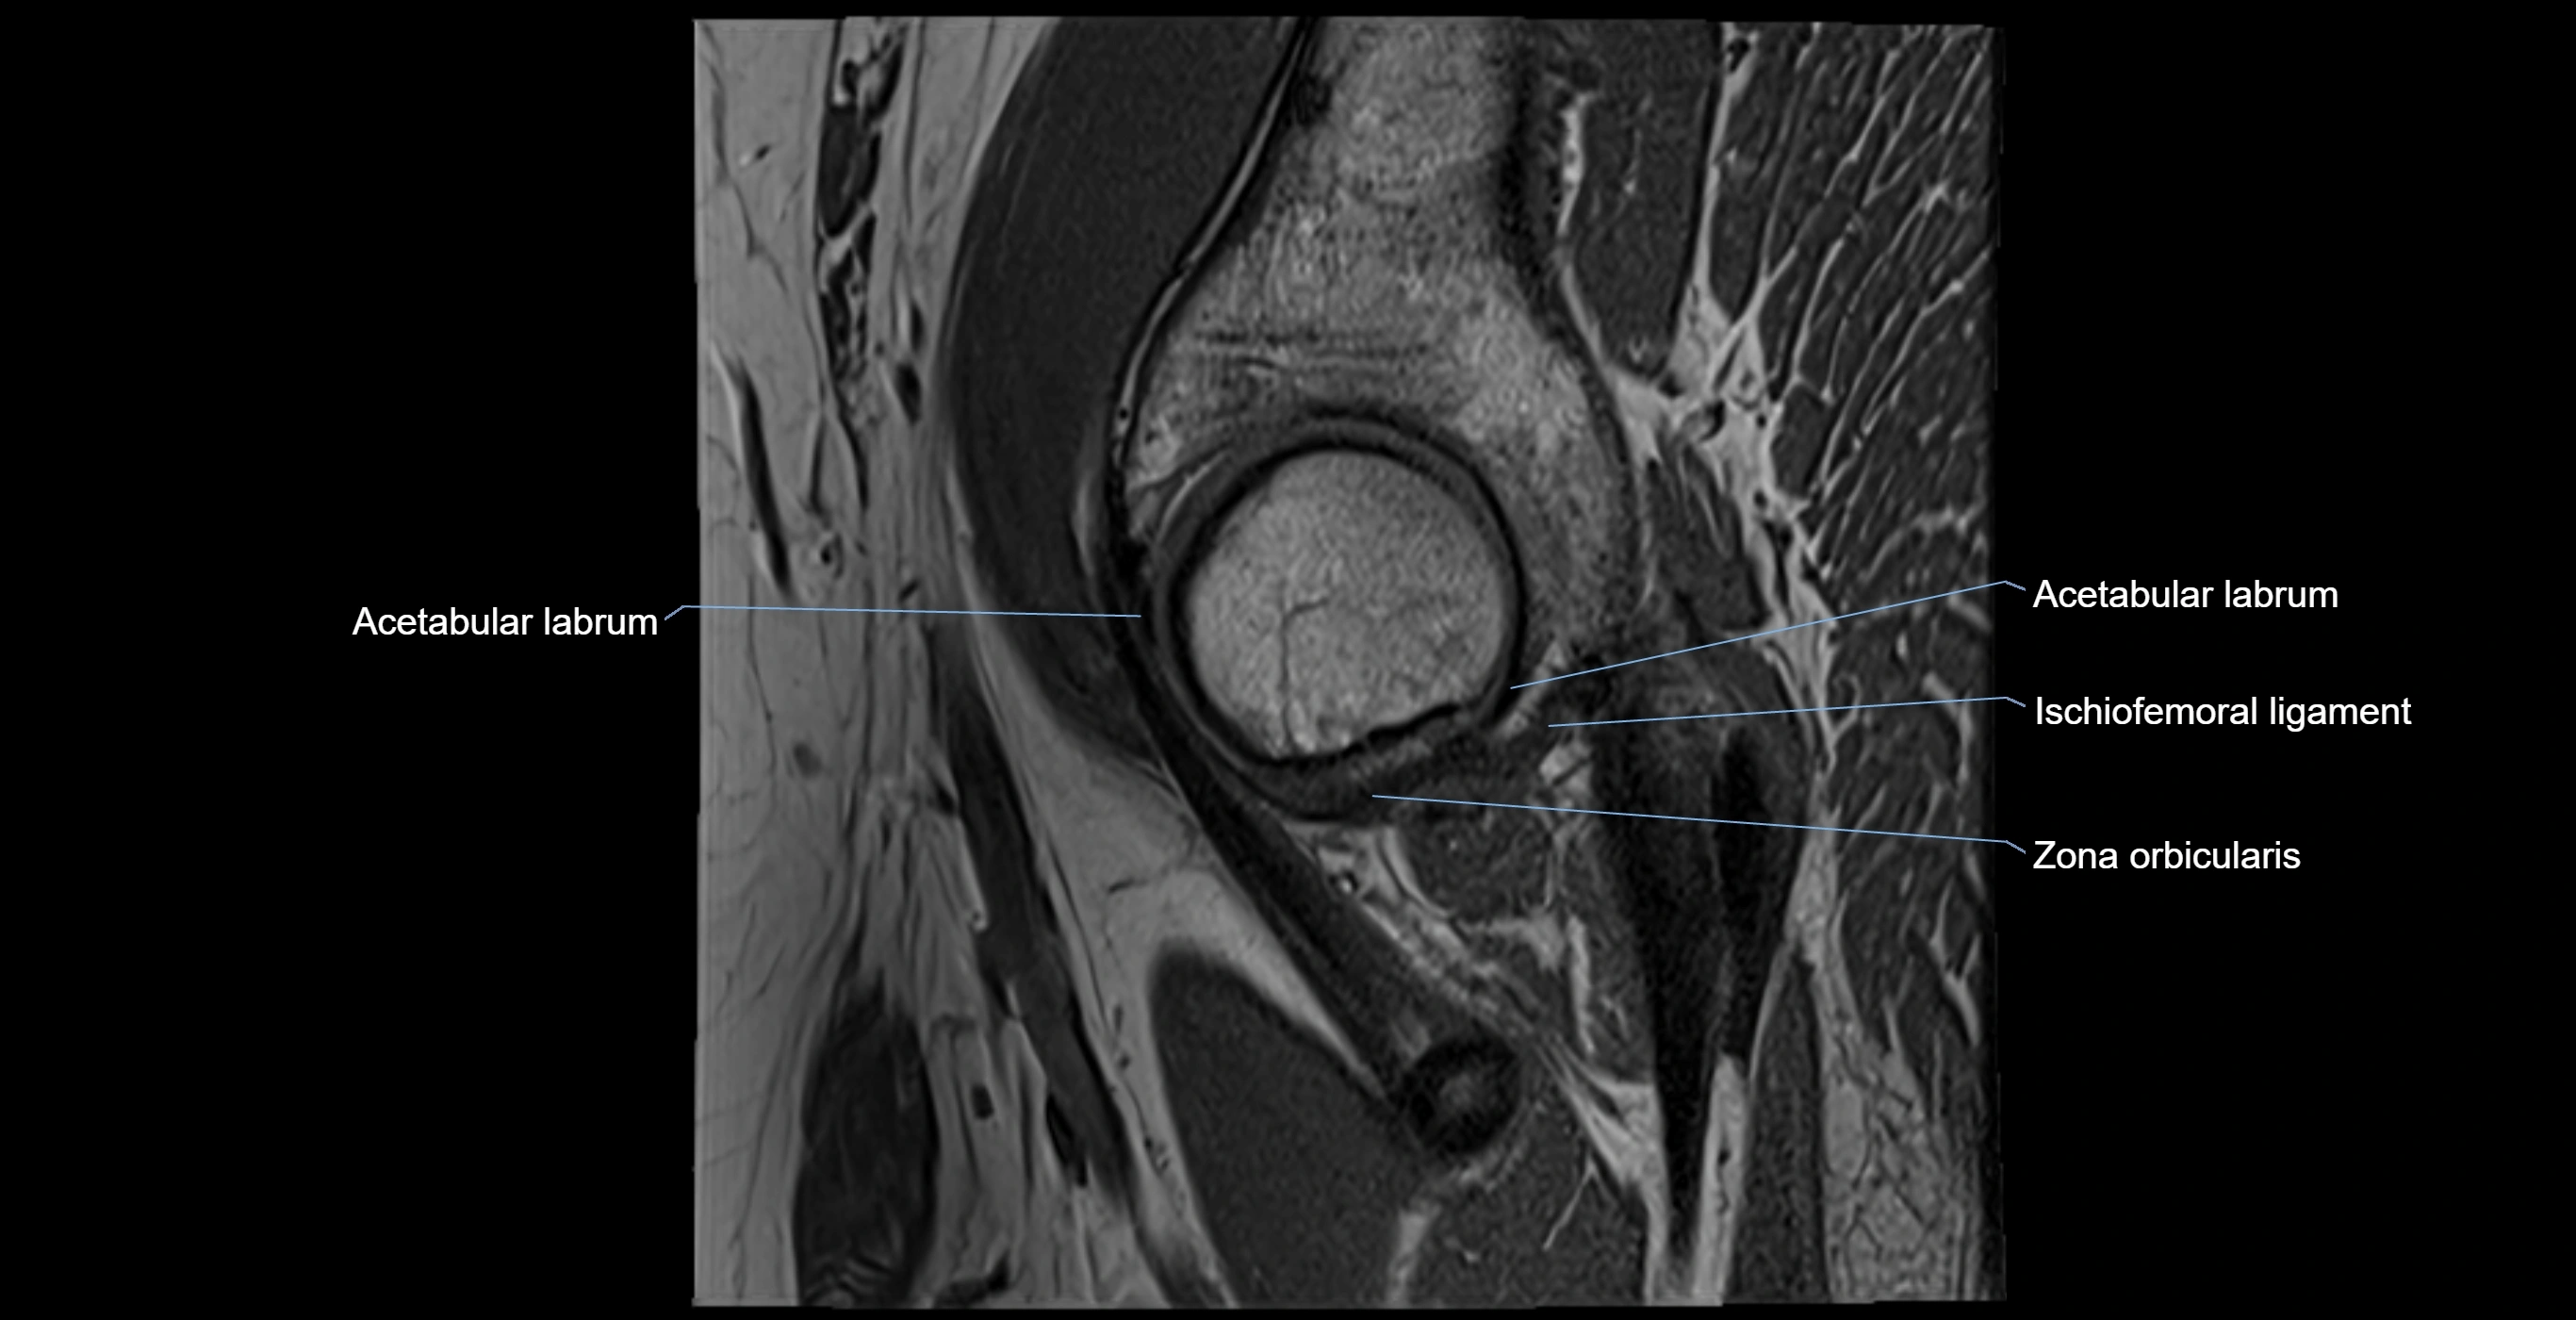

MRI Appearance

T1-weighted images:

• Labrum: low signal intensity (dark)

• Surrounded by intermediate signal joint fluid (bright on arthrogram)

• Tears: linear or focal areas of intermediate-to-high signal interrupting labral continuity

T2-weighted images:

• Joint fluid: bright, making labral tears visible as fluid extending into or around labrum

• Degeneration: may show areas of increased signal within labrum

MRI image

image